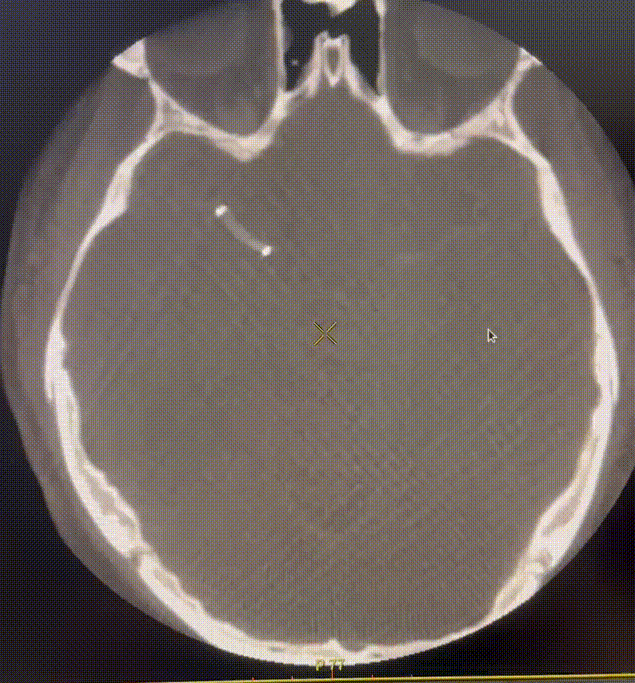

支架植入后造影提示残余狭窄约0%, 右侧大脑中动脉供血区供血较前明显改善,前向血流达到3级。患者麻醉复苏后无不适,恢复良好出院,继续双联抗血小板聚集及他汀类药物治疗。

术后即刻复查头CT提示:支架张开良好无造影剂渗漏。

动脉长鞘怎么置入一技之“长”丨经桡及经股困难入路应用赛诺神畅APEX TRA GC™导引导管建立通路病例合集_https://www.jmylbn.com_新闻资讯_第47张